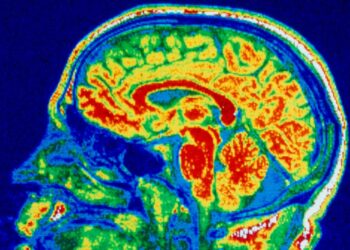

A screen image of Doom being played by human neurons on a chipCortical Labs A clump of human brain cells ...